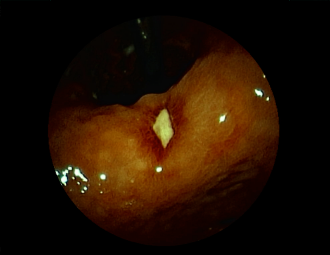

症例3:十二指腸潰瘍(53才男性)

1年前からの慢性胃痛を主訴に当院受診。十二指腸球部前壁に深くて大きな潰瘍(Stage A1)があり、潰瘍底は厚い白苔に覆われ、一部白苔のはみ出しを認める。潰瘍周囲粘膜は浮腫を伴っている。ボノプラザンフマル酸塩投薬で治療開始しました。

通常画像